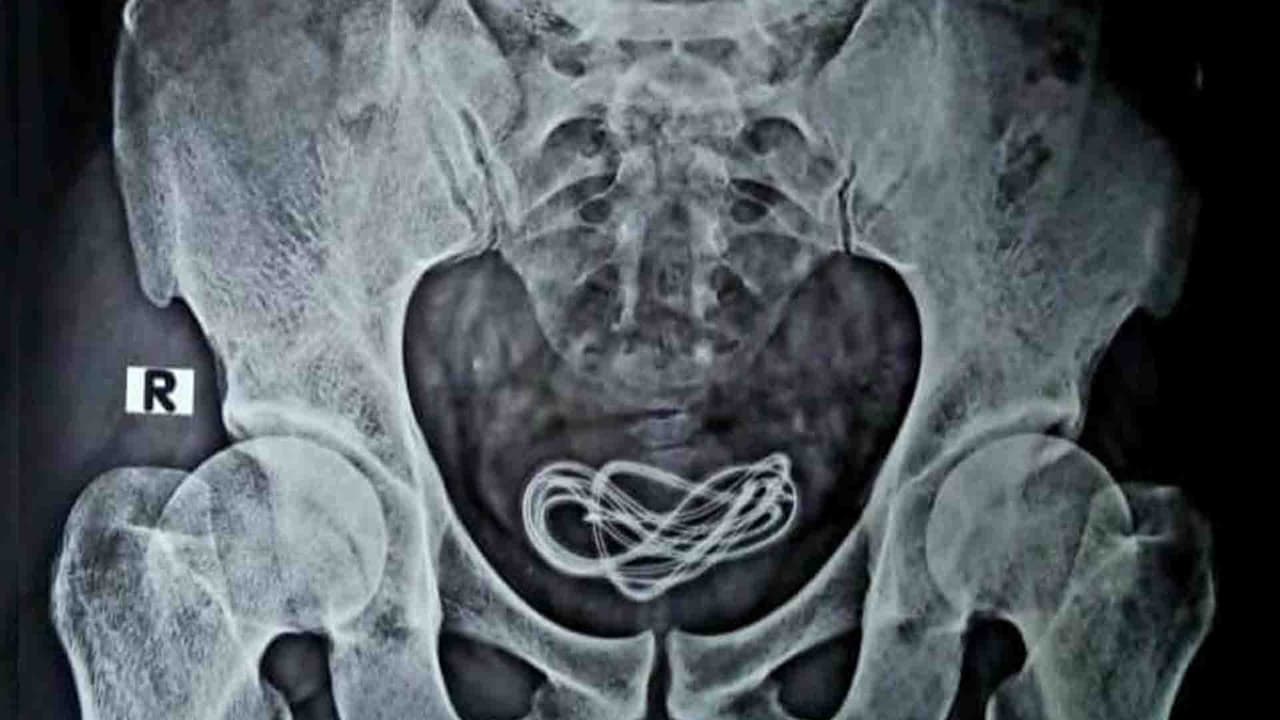

Doctores encuentran cargador de teléfono de 60 centímetros en la vejiga de un hombre

Este extraño caso fue reportado por médicos de la India, quienes recibieron a un paciente con intensos dolores abdominales, pero lo que encontraron es de no creer.